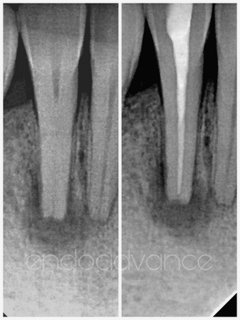

Αρχική ενδοδοντική θεραπεία σε 2ο κάτω γομφίο με μορφολογία C-shaped